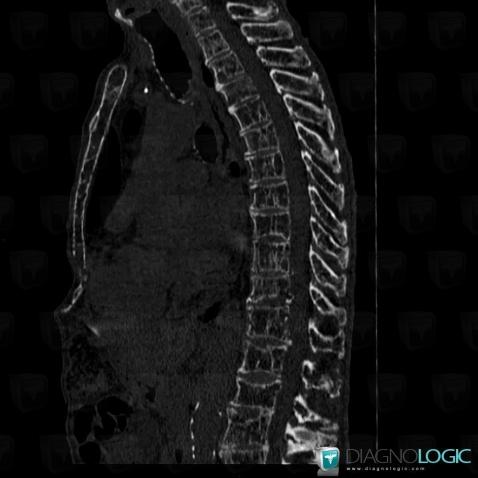

Multiple myeloma, Vertebral body / Disk, CT

Here is the specific information in the key image above:

- Diagnosis Multiple myeloma, Location(s) Vertebral body / Disk, with gamuts Lytic lesion in a vertebra